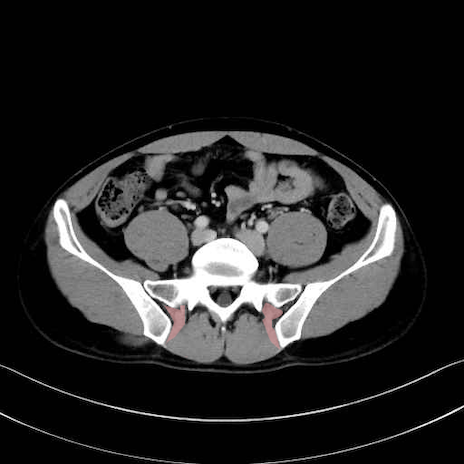

外閉鎖筋 (Obturator externus)